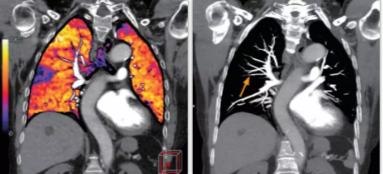

相比傳統(tǒng)成像方式,肺部柔性減影技術(shù)通過人工智能,對平掃數(shù)據(jù)和CT肺動(dòng)脈血管掃描數(shù)據(jù)進(jìn)行智能比對,解碼并識(shí)別各個(gè)器官(肺、氣管、肺動(dòng)脈、肺靜脈、主動(dòng)脈等)的空間位置,并在三維空間中進(jìn)行體素級(jí)的柔性配準(zhǔn),從而極大提升了不同序列數(shù)據(jù)的空間位置的一致性。通過肺部柔性減影技術(shù)可得到肺強(qiáng)化碘圖,可以顯示出傳統(tǒng)CTPA圖像看不到的小栓塞病變,提高了栓塞檢出率,其結(jié)果甚至可與SPECT吻合。

肺智能柔性減影成像功能發(fā)現(xiàn)亞段肺栓塞